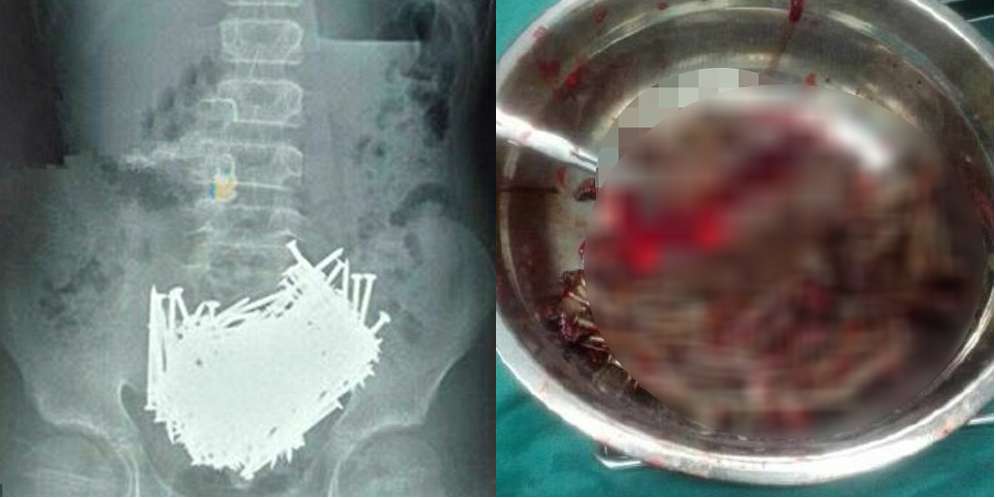

Petugas RSUD Dr. Soekardjo Menunjukkan Foto Rontgen Perut Wawan (Foto: Wartapriangan)

Laporan WartaPriangan menyebut, Wawan meninggal setelah dirawat intensif usai operasi pengangkatan paku di perutnya. Operasi pengangkatan 48 paku di perut Wawan berhasil dilakukan Tim Dokter RSUD Dr. Soekardjo.

Wawan mengatakan kepada Warta Priyangan awalnya merasakan sakit luar biasa di bagian perut. Saat menjalani rontgen di RSUD dr. Soekardjo, Kota Tasikmalaya, didapati benda menyerupai paku.

Saripudin, 34 tahun, adik kandung Wawan, mengatakan paku yang ditemukan tak hanya satu tapi berjumlah banyak.

" Kemarin kan di rontgen, dari hasil rontgen kemudian terlihat ada benda mirip paku di bagian perut kakak saya. Dan jumlahnya bukan satu, tapi banyak," ungkap Saripudin.